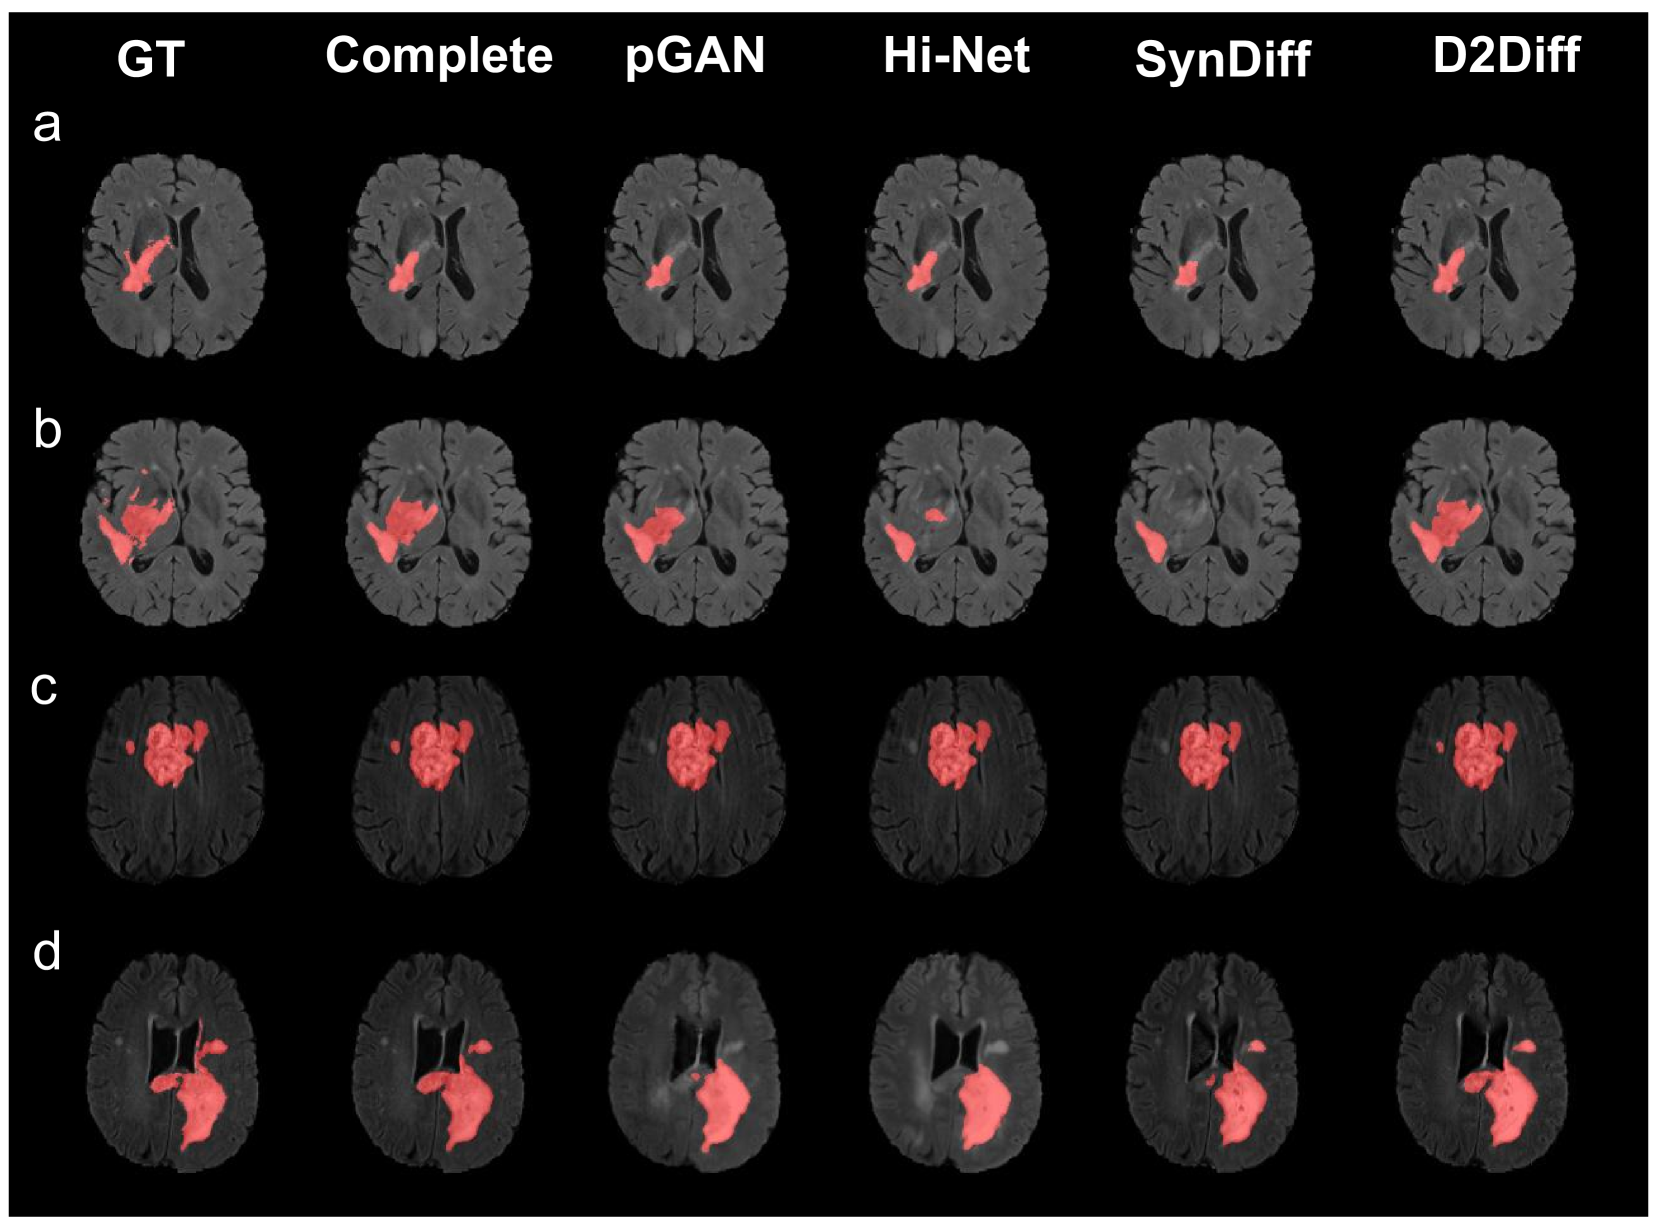

Downstream segmentation task performance.

To assess the diagnostic equivalence of our synthetic results, we conducted tumour segmentation using the BraTS dataset. A MONAI U-Net[22] was trained on all four contrasts to predict tumour masks with the same train-test split as synthesis tasks. Table 2 marks contrasts replaced by synthetic images during testing, with Dice scores for predicted masks. Fig 4 presents qualitative comparisons. The "Complete" setup represents segmentation using all actual test contrasts without synthetic replacements. For comparison, we selected top-performing methods from each category. Results show that D2Diff closely matches the "Complete" setup, demonstrating clinically reliable and plausible synthesis quality. Notably, D2Diff achieves slightly higher Dice scores, likely due to the dataset’s multi-site variability [17], including contrast differences and occasional artifacts. D2Diff’s diffusion-based dual-domain architecture effectively mitigates these artifacts and handles contrast variations more robustly, leading to improved segmentation performance.

Figure 4: Segmentation results.

Task Contrasts Dice Score% ↑

T1 T2 FLAIR T1CE pGAN Hi-Net SynDiff D2Diff

a x 80.5 80.02 80.91 81.05

b x x 80.64 79.70 80.81 81.19

c x x x 79.96 78.93 80.66 81.02

d x x x x 76.50 73.49 79.31 79.34

complete 80.83

Table 2: Segmentation performance.